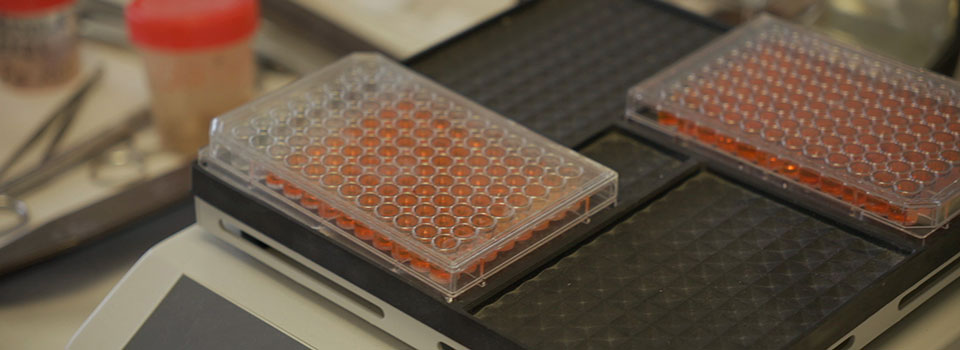

INVESTIGANDO EL SÍNDROME DE QUILOMICRONEMIA FAMILIARCedecomProduccion-Audiovisual2025-04-11T20:11:43+02:00